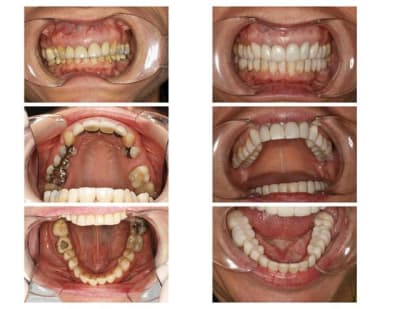

1 mois plus tard, la suite...

Photo de départ, pour vous aider.

Photo des tempos (haut et bas) avec la nouvelle occlusion, après 4 semaines en bouche.

Les 6 tempo sur les ant. sup. ont été placées après la chirurgie parodontale et la dépose des anciennes couronne il y a 4 mois.

Pas de commentaire sur l'esthétique des tempo du bas et post. haut : on voit les racines et les vieilles restauration au travers, normal, il n'y a pas eu de taille. Aussi des détails de formes à corriger avec les céramiques, à ce stade, aucune importance.

Commentaires de la patiente : que du positif (adaptation facile, fonction, aspect du visage + profil nettement mieux, musculature plus détendue).

Dans 1 mois, je taille et place le haut en céramique, en 2 rdv. Puis attente de 4 semaines pour re-vérifier l'occlusion en 3D avec le bas en "tempo", et taille et pose du bas, en 2 rdv.

Autres photos dans 2 mois environ ...